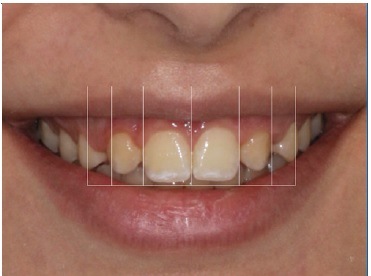

Orthodontic treatment involving space closure was performed. After golden proportion (Figure 4) and Bolton’s anterior analysis, the presence of a 77.7% dental discrepancy in the anterior relation with mandibular excess was confirmed (14, 13, 11, 21, 23, 24, / 33, 32, 31, 41, 42, 43). Due to the agenesis of the maxillary lateral incisors and the need to perform esthetic restorations in the upper arch to improve smile harmony, a similar Bolton anterior discrepancy of 76% was obtained after restorations. After orthodontic treatment, shade selection was accomplished using a Vita Shade Guide (Figure 5), and dental bleaching was performed. Afterward, according to clinical findings and with careful consideration of all treatment options available for rehabilitation, it was decided that the maxillary canines and first premolars would be additively remodeled to the shape of lateral incisors and canines, respectively, using direct composite (Figure 6), which provides advantages in symmetrical cases.

A 15-year-old patient presented with unilateral MLIA and microdontia (Figure 9). The left maxillary canine erupted mesially from its normal position, while the right maxillary lateral incisor was conical. Both central incisors were tipped to the left and associated with occlusal plane canting to the left. There was also an evident Bolton’s anterior discrepancy of 74.1 % (13, 12, 11, 21, 23, 24 / 43,42, 81, 71, 32, 33) due to maxillary asymmetric agenesis, a canine in place of the lateral incisor, and a conical contralateral (Figure 10). And due to agenesis of the mandibular central incisors and the presence of correspondent deciduous teeth. After the orthodontic treatment (Figure 11), the complexity of the asymmetric case required digital smile planning (Figure 12) and a diagnosis wax-up (Figure 13) to plan and visually demonstrate the desired result to the patient.